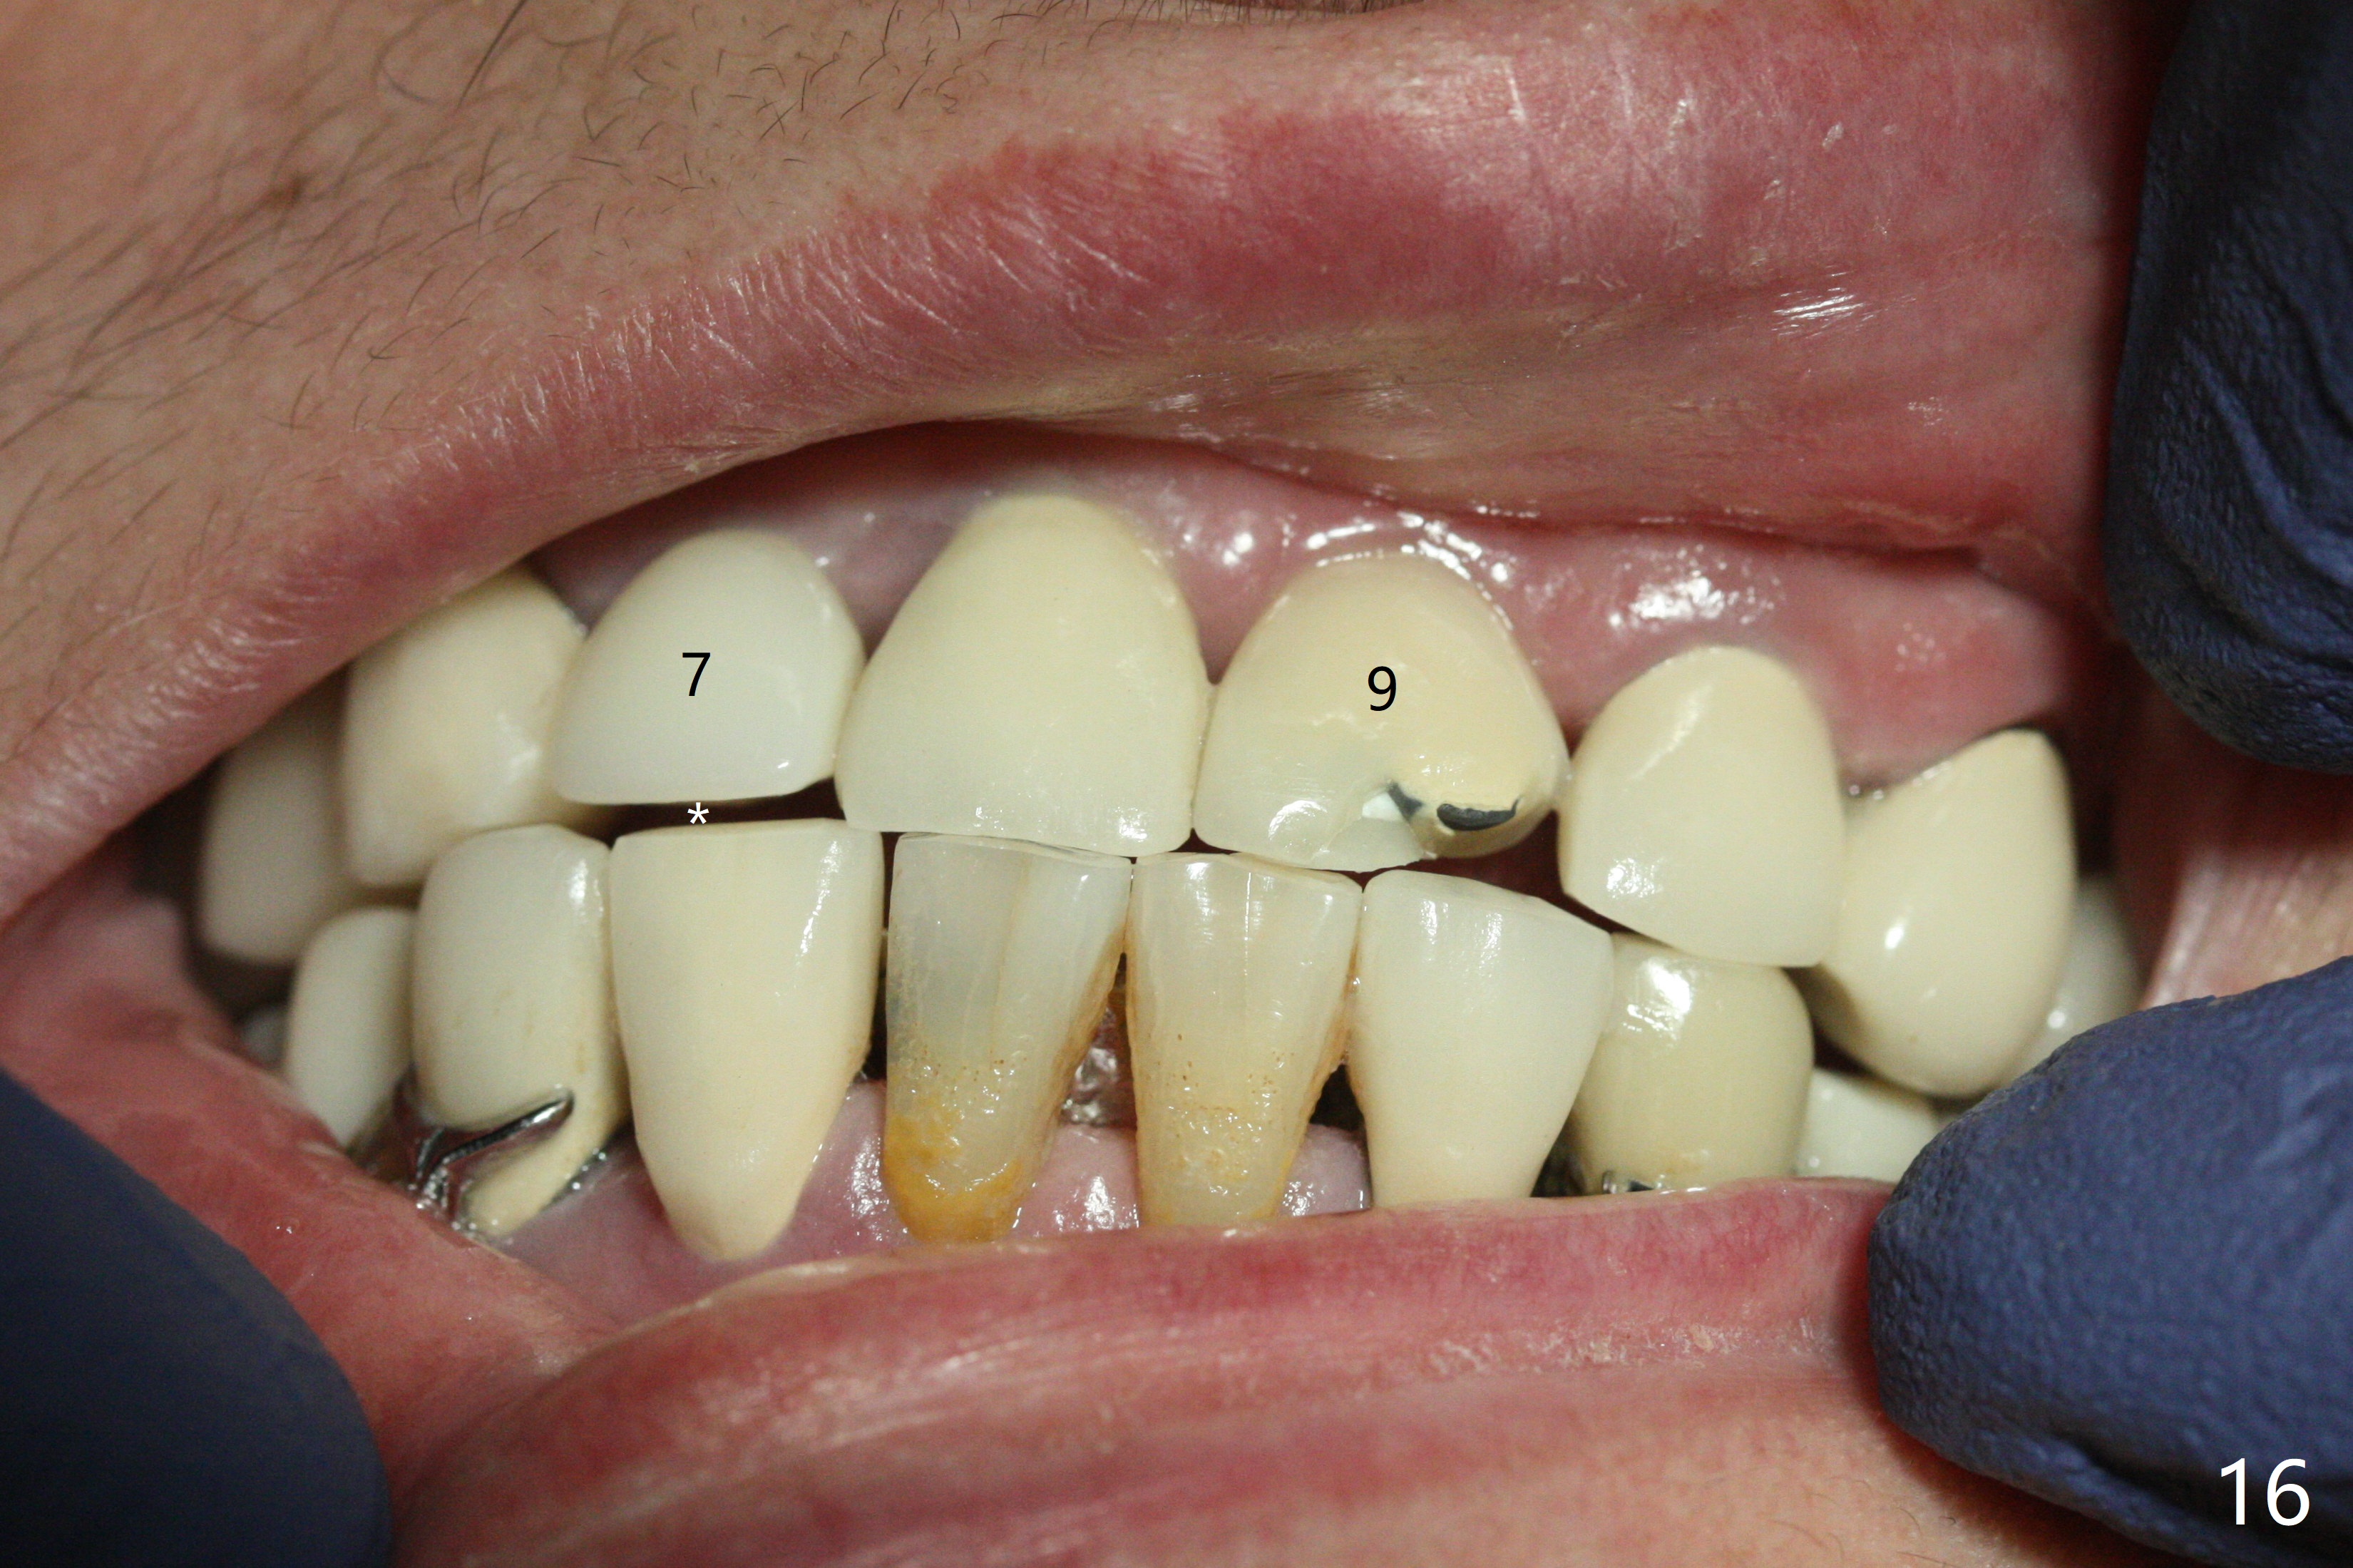

The buccal contour at #9 seems to be slightly concave preop (Fig.1,2 (*)). In fact the buccal plate is found to be lost when the tooth is extracted. Osteotomy is initiated as palatal as possible apical, but the occlusion dictates the coronal end of the osteotomy should be buccal, leaving the buccal gap ~ 2 mm for bone graft. The initial osteotomy (18 mm deep) appears to be close to the Incisive Foramen (Fig.3 blue dashed line). The nasal floor appears to be intact when the drill is removed. Subsequent osteotomy is adjusted so that the apical end of the osteotomy moves distal; when a 3.8x15 mm dummy implant is partially placed, there is clearance (Fig.4). It remains so when a definitive implant is seated (Fig.5); Vanilla graft is placed (Fig.5 *) before placement of a 4.5x5.5(3) mm abutment. More allograft is placed when an immediate provisional is fabricated (Fig.6 arrow and *). The gingiva remains to be recessive 1 month postop (Fig.7). It seems to be related to the bulky gingival margin of the provisional (Fig.8 *). After trimming the latter (Fig.9 *), the gingival margin immediately returns close to normal (Fig.10). The gingival margin is even between #8 and 9 two months postop, but the bone graft is exposed apically (Fig.11 ^). It may heals by itself. Otherwise debridement, regraft, PRF and suture are pending. The coronal portion of the socket heals 4 months postop (Fig.12). The gingival cuff forms by the immediate provisional (which is removed for impression) 4 months postop (Fig.13 *). While the full Zirconia crown at #7 remains intact (Fig.14), the PFM at #9 has porcelain chip (Fig.15). It is partially due to the occlusion; while the crown at #7 has clearance with the opposing dentition (Fig.16 *), the one at #9 has no. The access hole at #9 (Fig.17 *) seems to weaken the crown structure. There is no access hole at #7. No solid posterior support is another contributing factor for chip (Fig.18). The buccal plate has mild atrophy at #7 and 9 (Fig.19 *). A piece of bone graft is being expelled apically at #9 (Fig.20 >) and is removed subsequently (Fig.21). Before impression for repacking porcelain, the opposing incisal edge has been shortened (Fig.22 arrows, as compared to Fig.16). Since the ideal access hole is at the incisal edge (Fig.25 black circle), buccal to the existing one (Fig.24 A), the abutment is torqued before the repaired crown is recemented (Fig.23). Finally the crown has occlusal clearance (Fig.26). Porcelain chips again around the access hole of PFM 1.5 years post 2nd cementation. The dense bone at the crest (*) cannot explain why the abutment is not loose, since it remains incompletely seated (>). As it was trimmed short, an angled abutment is used (Fig.28). The coronal end is lingual, while #9/24 is edge to edge. The lingual aspect of the coronal end of the abutment is heavily trimmed to reduce bulkiness. To prevent chip, Zirconium crown will be fabricated in spite of the fact that it does not match the PFM of #8 (potential shade discrepancy). The patient is pleased with the new Zirconia crown (Fig.29).